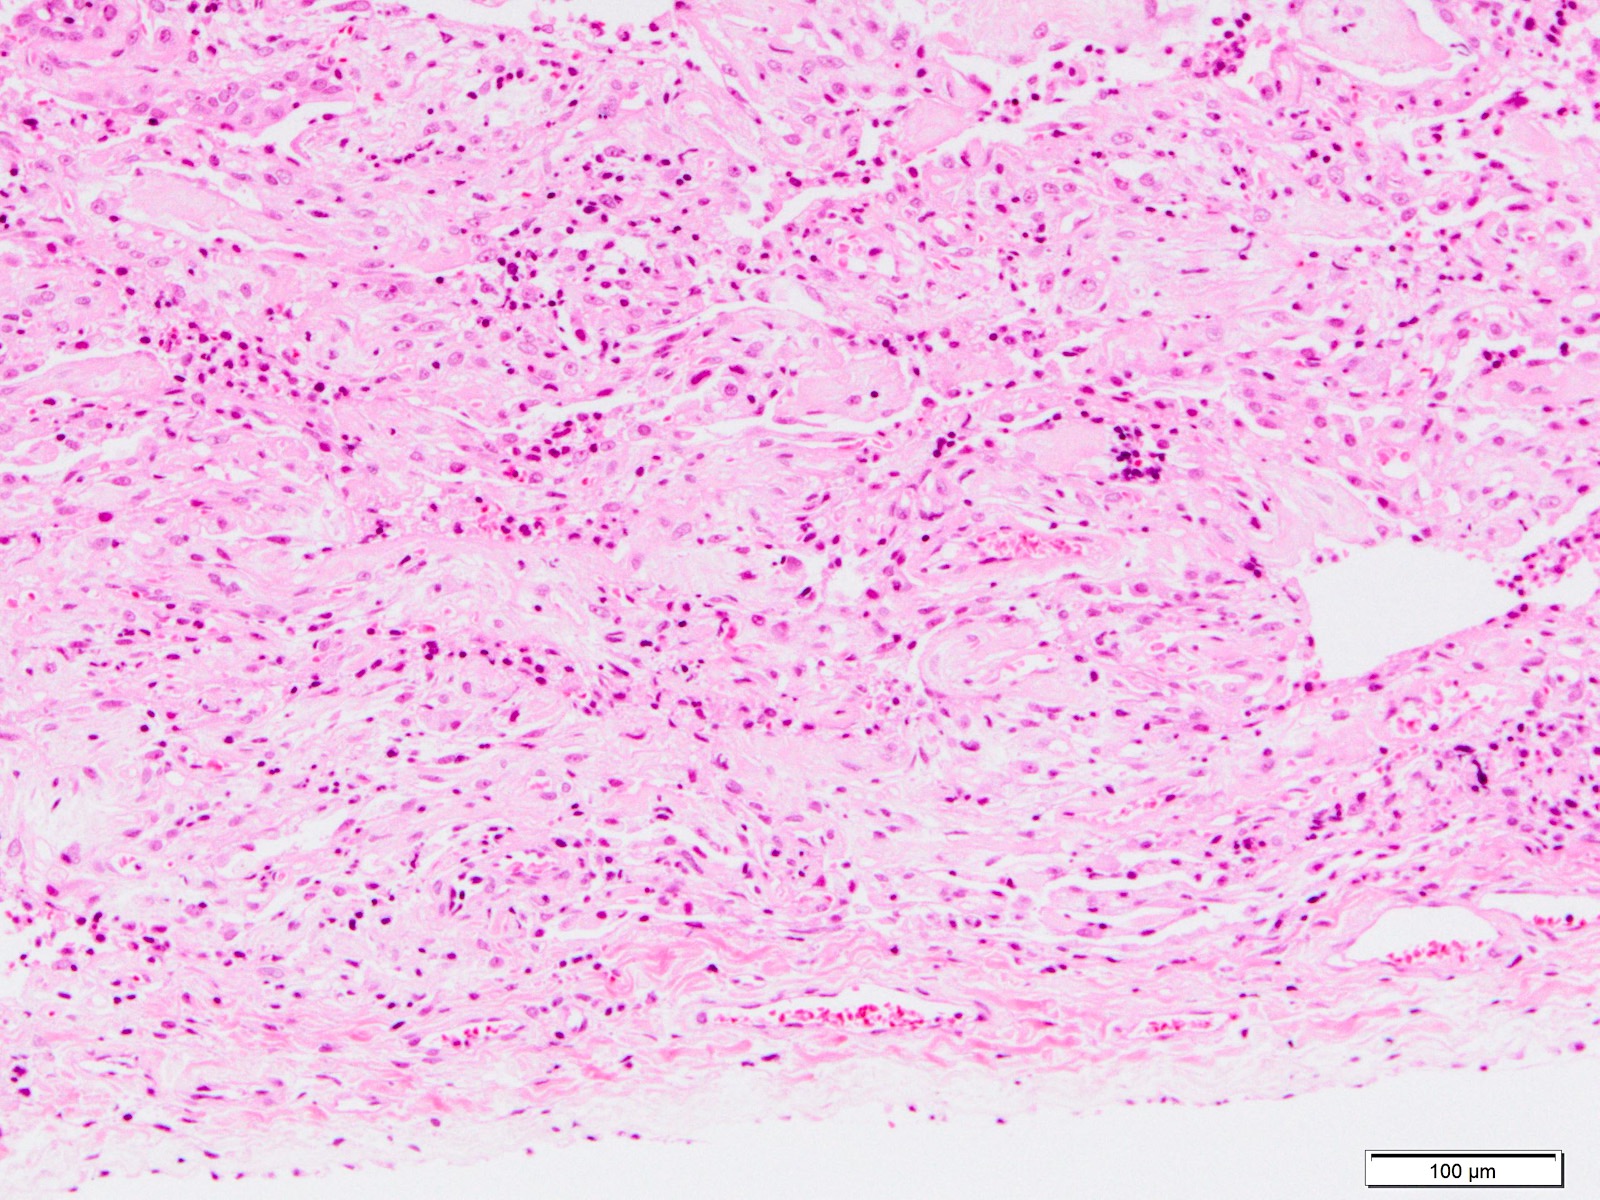

Microscopic (histologic) description

- Histopathology of DAD progresses from exudative (acute) phase through proliferative / organizing (subacute) phase to chronic fibrotic phase roughly corresponding to the period of ARDS (Am J Pathol 1976;85:209, Arch Pathol Lab Med 2010;134:719, Clin Chest Med 2000;21:435, N Engl J Med 2000;342:1334)

- Proliferative / organizing (subacute) phase

- Alveolar change

- Remnants of hyaline membrane with or without organization

- Interstitial and intra-alveolar proliferation of myofibroblasts

- Lymphocytic infiltration

- Epithelial change

- Proliferation / hyperplasia of type II pneumocytes

- Vascular change

- Endothelial injury and thromboemboli in arterioles

- Alveolar change

- Fibrosis phase

- Alveolar change

- Collagenous fibrosis

- Microscopic honeycomb-like change

- Traction bronchiolectasis

- Epithelial change

- Squamous metaplasia / hyperplasia

- Vascular change

- Remodeling of arteries

- Intimal fibrosis

- Thickening of media

- Alveolar change

Microscopic (histologic) images

Contributed by Akira Yoshikawa, M.D. and Yale Rosen, M.D.